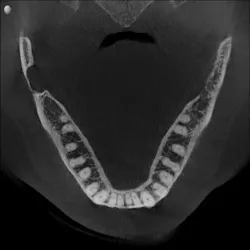

As part of our intake process to make a sleep mandibular advancement device, we take a cone beam image (figures 1–4). This way we can evaluate sinuses, septum, turbinates, teeth, and jaws.

Upon examination, it was noted that a dark, radiolucent lesion was present on the lower right jaw, anterior to the angle of the mandible. The patient didn’t have any pain, symptoms, or knowledge of the lesion. It was not palpable. He reported that he had his third molars removed in his twenties with no complications.

The Stafne defect is code for a depression in the bone, a concavity, due to the submandibular gland. In addition, it can’t be qualified as a cyst because there is no epithelial lining or fluid content. It does usually occur more in men as well.1 There is no treatment necessary; it’s something we can just monitor.